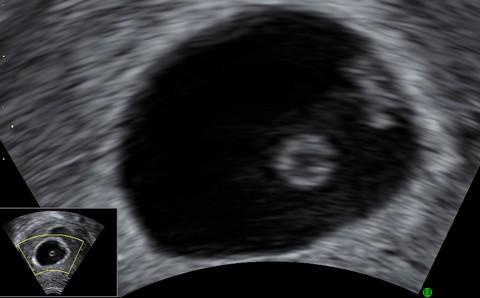

V tomto týdnu již lékař dobře vidí na ultrazvuku „bušící“ srdce vašeho budoucího miminka.

V tomto týdnu se vyvíjejí důležité orgány dítěte, je proto velmi zranitelné. Vyvarujte se jakýchkoli možných rizik včetně stresu, která by tento vývoj mohla narušit. Jdete v tomto týdnu na ultrazvukové vyšetření? Uvidíte, jak vašemu miminku tluče srdíčko.

V 7. týdnu těhotenství měří embryo zhruba 8 mm.Při zjišťování délky embrya se měří vzdálenost od temene ke kostrči. Váha embrya je nyní zhruba 1 gram.

Snímek z ultrazvuku pochází z 6+5, tedy ukončeného 6. týdne + 5 dní ze sedméno, je vidět žloutkový váček s náznaky struktury plodu o velikosti 9 mm.